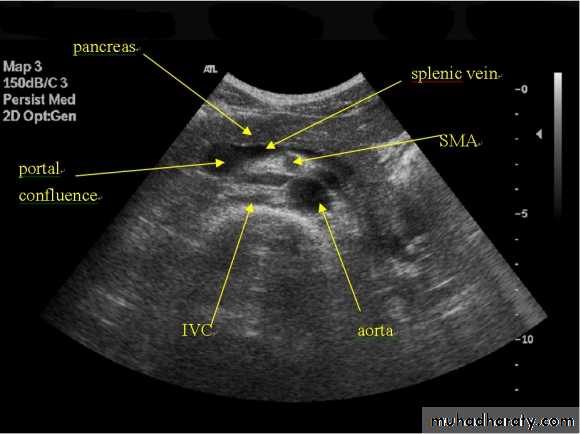

Acute Pancreatitis

CT used to

• 1. Pancreatic necrosis .• 2. An abscess.

• 3. Vascular complications.

• 4. Pseudocyst

1

3

2

4

Chronic pancreatitis

Pancreatic carcinoma